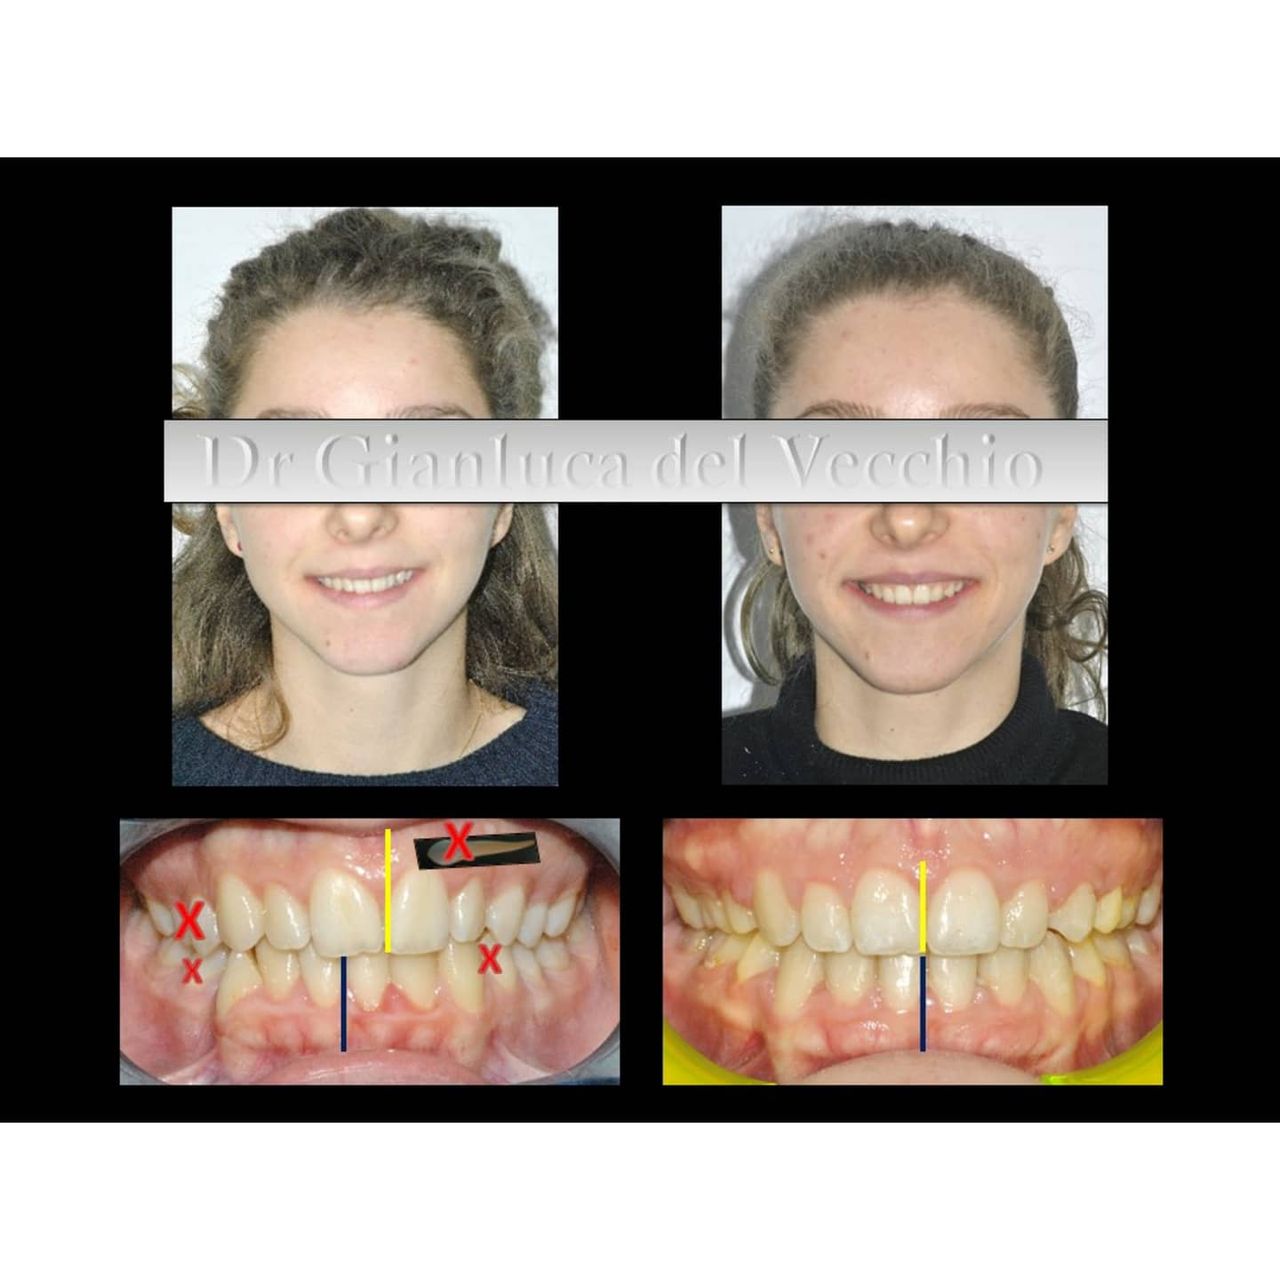

Il dottor Gianluca del Vecchio si occupa esclusivamente di ortognatodonzia, grazie anche alla collaborazione multidisciplinare di una équipe davvero entusiasmante e all’utilizzo di strumenti diagnostici e terapeutici all’avanguardia in ortognatodonzia. Particolare è la sua capacità di condurre i giovani pazienti ad affrontare, nella massima sicurezza emotiva e clinica, qualsiasi eventuale condizione di dolore derivante, ad esempio, da carie o da altre patologie, ma soprattutto di risolvere tutte quelle condizioni di “denti storti”, così spesso causa di disagio psicologico o di fenomeni deprecabili, quale il bullismo.

Queste le ragioni che consentono di trattare le malocclusioni, sia dei bambini che degli adulti, con protocolli scientificamente validati come i più veloci, affidabili e confortevoli.

Il dottore ha acquisito una concezione quanto più pratica e moderna della disciplina e utilizza apparecchietti di diversi colori di tipo mobile e fisso, ma anche terapie sia estetiche che invisibili, fiore all’occhiello di poche realtà in Italia. Per terapie estetiche e invisibili si intendono quelle in grado di spostare i denti, senza che traspaia nulla dalla bocca o con stelline e fili bianchi, esattamente come i denti del paziente.